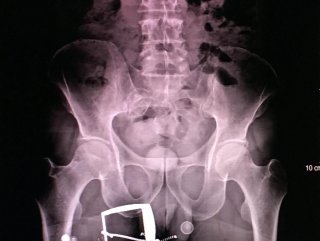

İranlı kadının makatında 124 gram uyuşturucu çıktı